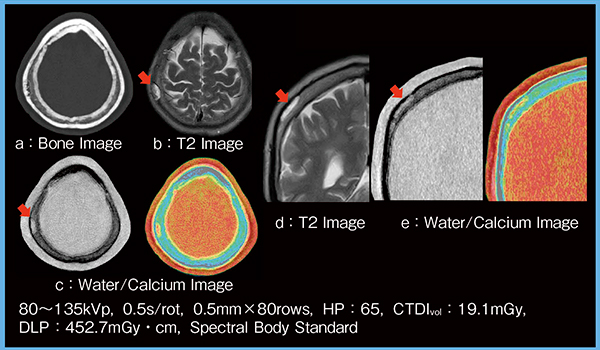

症例5(図7)は頭蓋骨海綿状血管腫であるが,MRI(b,d)で明瞭な腫瘍の広がり(→)を,Water/Calcium Image(c,e)でも同様に確認可能であり,CT検査の付加情報としての有用性が期待できる。

図7 症例5:Water/Calcium Imageによる腫瘍の広がりの評価(頭蓋骨海綿状血管腫)